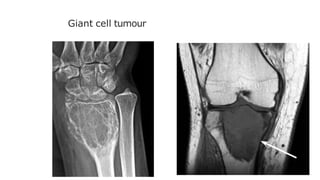

Giant cell tumour

Has features of both malignant and benign tumours.

It is locally invasive but rarely metastasizes.

It occurs most commonly around the knee and at the

wrist after the epiphyses have fused. It isan expanding

destructive lesion, which is subarticular in position